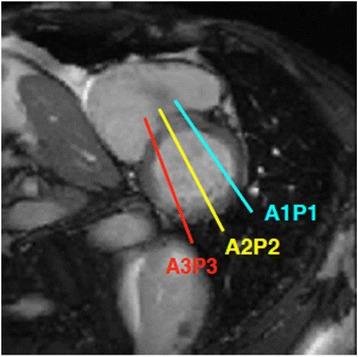

Over the last 25 years, cardiovascular magnetic resonance imaging (CMR) has emerged as an alternative to echocardiography for assessment of valvular heart disease (VHD). Although echo remains the first-line imaging modality for the assessment of patients with VHD, CMR can now provide a comprehensive assessment in many instances. Using a combination of techniques, CMR provides information on valve anatomy and enables quantitative analysis of the severity of the valve lesion.

In this review, the fundamentals of CMR in assessment of VHD are described, together with its strengths and weaknesses. We detail the utility of CMR for studying all aspects of VHD, including valve anatomy, flow quantification as well as ventricular volumes and function. The optimisation of CMR for evaluating the commonest valve lesions (aortic stenosis, aortic regurgitation, mitral regurgitation, mitral stenosis) as well as in right-sided VHD and prosthetic valves is summarised. The focus of this review is to enable the reader to optimise the use of CMR in his or her own evaluation of heart valve lesions in clinical practice.

在过去25年中,心血管磁共振成像(CMR)已成为评估瓣膜性心脏病(VHD)的超声心动图替代方法。尽管超声仍然是评估VHD患者的一线成像方式,但CMR现在在许多情况下可以提供全面评估。通过结合多种技术,CMR可提供瓣膜解剖结构信息,并能对瓣膜病变的严重程度进行定量分析。

在本综述中,描述了CMR评估VHD的基本原理及其优缺点。我们详细阐述了CMR在研究VHD各个方面的实用性,包括瓣膜解剖结构、血流定量以及心室容积和功能。总结了CMR评估最常见瓣膜病变(主动脉瓣狭窄、主动脉瓣反流、二尖瓣反流、二尖瓣狭窄)以及右侧VHD和人工瓣膜时的优化方法。本综述的重点是使读者能够在临床实践中优化CMR在其自身对心脏瓣膜病变评估中的应用。